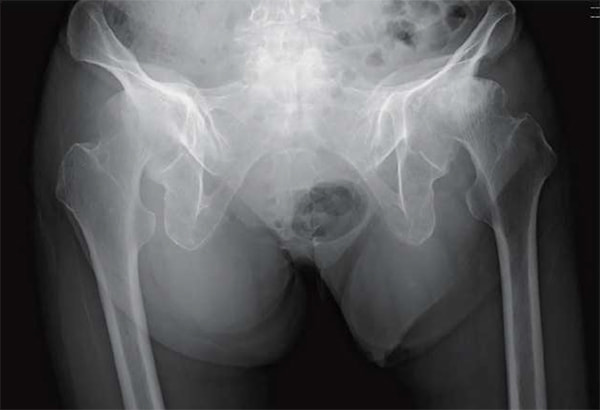

人工股関節置換術において従来の後側方アプローチ(Posteo Lateral Approach)に加えて、2015年より前方アプローチ(Direct Anterior Approach)を積極的に取り入れて参りました。

これは脱臼率の低下に加えて、筋間アプローチによる低侵襲手術を提供するという目的によるものです。これにより在院日数は低下し、術後の姿位制限を撤廃したことで、前述のスポーツ復帰率の向上を図ることができるようになりました。また、高齢化に伴い生じる脊椎変形、脊椎固定術後の矢状断アライメントの変化に対応できるよう、CUPは透視を用いて動的に評価しながら至適位置に設置することで良好なstabilityが得られています。

仰臥位股関節Xp

立位股関節Xp

立位で骨盤後傾を伴う

術後 立位股関節Xp